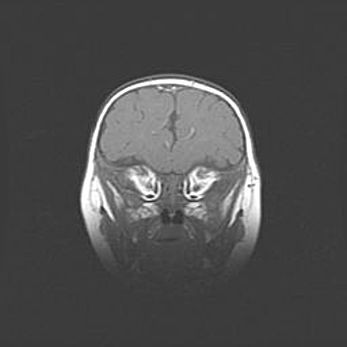

Наружная гидроцефалия с возможной атрофией височных областей.

Возраст: 28 дней

Вес: 3670 г

Пол: мужской

Окружность головы: 38 см

Срок гестации: 40 недель

Гидроцефалия головного мозга у новорожденных – это заболевание, которое характеризуется скоплением избыточного количества спинномозговой жидкости в желудочковой системе головного мозга в результате затруднения её перемещения от места выработки к месту поглощения в кровеносную систему или вследствие нарушения абсорбции. При открытой наружной форме гидроцефалии у новорожденных расширяются и переполняются субарахноидные пространства.

При нормотензивных  формах,  которые,  как  правило,  являются  следствием  перенесенных ишемических  повреждений  паренхимы  мозга,  возможно  сочетание микроцефалии  с нормотензивной гидроцефалией. В основе данных изменений лежит атрофия больших полушарий с преимущественной  локализацией  в  лобно-височных  областях.